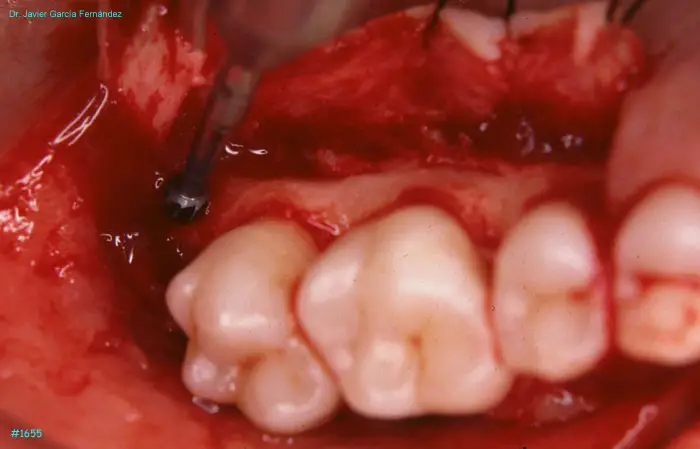

Atlas of Surgical Techniques in Periodontics. Chapter IV. Atlas de Técnicas Quirúrgica en Periodoncia

image 168